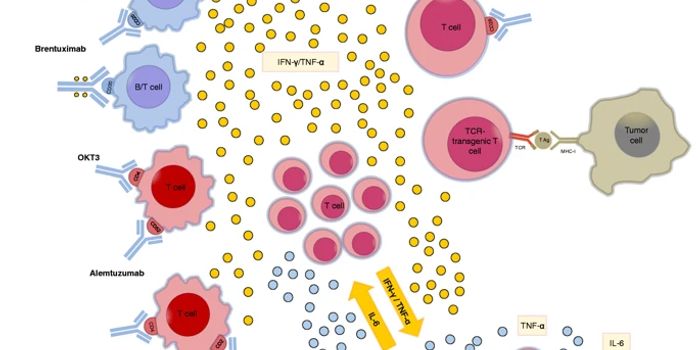

FEB 13, 2025ImmunologyImmunotherapy has changed the way physicians treat cancer patients. This approach to therapy targets the immune system t ...

DEC 19, 2024ImmunologyImmunotherapy has transformed the field of cancer medicine. It has extended survival rates, reduced toxicity, and, in so ...

DEC 12, 2024ImmunologyImmunotherapy has changed the way physicians treat patients and has improved standard of care for many different tumors. ...